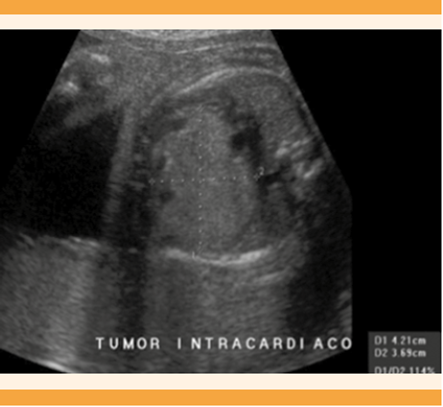

En cuanto a la clasificación de tumores únicos o múltiples se encontraron cuatro casos con tumores únicos (57%) y tres con múltiples (43%). El de mayor tamaño fue de 42 x 36 mm (Figura 1) y el más pequeño, de 3 x 3 mm (Cuadro 1).

Figura 1 Corte de cuatro cámaras cardiacas donde se observa un rabdomioma en el ventrículo izquierdo (Caso 5).

Figura 3 Tumor intracardiaco que ocupa la totalidad del área cardiaca en corte axial de tórax (Caso 7).